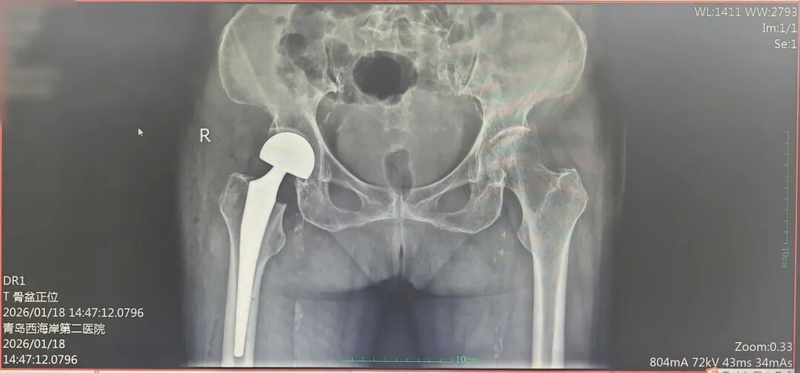

关节外科单彬主治医师提前定制围手术期快速康复(ERAS)管理方案,优化术前、术中和术后处理措施,实现快速康复、缩短住院时间、降低并发症发生率和再入院风险;并结合影像学检查(术前影像显示股骨颈移位明显),联合李阳副主任医师共同制定手术方案,确定实施右髋人工股骨头置换术,以最小创伤实现快速康复。麻醉科全面评估老人心肺功能,量身定制个体化麻醉方案,通过精准用药提前控制血压、血糖及心律失常,将麻醉风险降到最低;心内科全程深度参与,指导围手术期心血管用药,积极转复心律,实时监测心脏功能,为手术期间的循环稳定保驾护航。

1月16日下午,在入院仅24小时后,手术正式启动。单彬主治医师与李阳副主任医师默契配合,麻醉科、心内科团队全程保驾护航,整个手术过程仅用1小时便顺利完成,术中出血量仅约 150ml。

术后,老人意识清醒,平稳返回病房。护理团队第一时间协助进行下肢功能锻炼,加速康复进程。让人惊喜的是,术后第二天(48小时内),老人就在助行器的辅助下成功站立,缓慢迈出了康复的第一步!影像复查显示,假置、大小精准适配,各项血液动力学及感染指标均平稳正常。